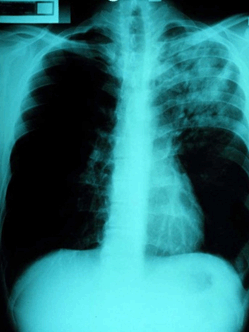

Pneumonia is the most common presentation of melioidosis, accounting for roughly half of all cases (Fig2). This finding is consistent across a wide variety of studies in different areas2,20,38,40-43, and is more commonly due to haematogenous dissemination to the lungs rather than inhalation of the pathogen44. The severity of the condition varies widely, from septic shock to mild undifferentiated pneumonia. Septic shock patients may present acutely unwell with high fevers and only slight cough or pleuritic pain, whereas patients with undifferentiated pneumonia will present with a more predominant cough accompanied by sputum and dyspnoea44. Radiography may range from diffuse nodular infiltrates in both lungs of septic shock patients to discrete and progressive consolidation in one or more lobes for those with undifferentiated pneumonia. It is most commonly found in the upper lobes, and pleural effusions and empyema may occur, particularly with lower lobe disease41,45. Melioidosis may be mistaken for tuberculosis and thus a high index of suspicion is required, particularly when encountering such cases in endemic areas. B. pseudomallei pneumonia is often associated with disseminated disease, causing septic shock and multi-organ dysfunction.

Figure 2: Chest X-ray showing left upper lobe pneumonia caused by Burkholderia pseudomallei (courtesy Dr Robert Norton, Director of Pathology, Townsville Hospital).